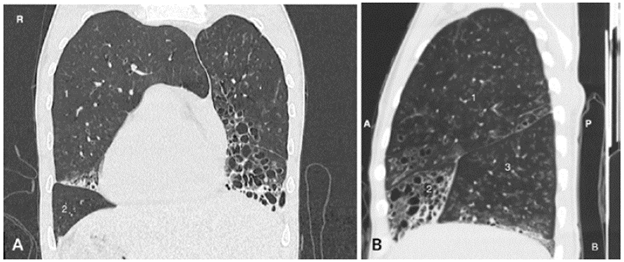

Symptomatology was interpreted as an infectious picture of low respiratory tract origin and possible bacterial sinusitis, for which antibiotic management was initiated with ampicillin sulbactam. Further paraclinical tests included a chest x-ray that showed dextrocardia, with no signs of consolidation or pleural effusion. This was complemented with high-resolution computed tomography (HRCT) (Figures 1 and 2) and a computed tomography (CT) of the paranasal sinuses (Figure 3).

High-resolution computed tomography of the chest on 80-channel tomograph. A) right aortic arch; B) cardiac apex to the right of the midline with multiple cylindrical and sacular bronchiectasis; C) multiple micronodules with a "tree-in-bud" pattern suggesting infection.

Figure 1: High-resolution computed tomography of the chest on 80-channel tomograph. A) right aortic arch; B) cardiac apex to the right of the midline with multiple cylindrical and sacular bronchiectasis; C) multiple micronodules with a "tree-in-bud" pattern suggesting infection.

Source: Document obtained during the study.